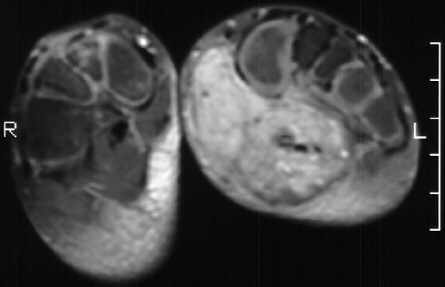

A 6 year old female presented to Outpatient Clinic with mass in her

left foot which the mother says has been getting bigger and causes pain

when the child walks for more than a few steps. There was firm tender mass

within the planter arch area of the left foot. the mass was approximately

6.5 x l7 cm. It involved virtually the entire arch of the foot. An xray

embolisation of left foot arteriovenous malformation. The current MRI is

above.

MRI is the most specific study to define the borders of a hemangioma for

which surgical excision is planned.